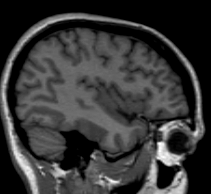

The insular cortex is “hidden” between the temporal and inferior parietal corticies. By drawing sulci lines in the sagittal view, we gain an outline of it in the coronal. Choose a sagittal slice where insula is clearly visible (Fig 1), then draw a “circle” around it (Fig 2). Do this for several slices and for both hemispheres.

Figure 1              Figure

2